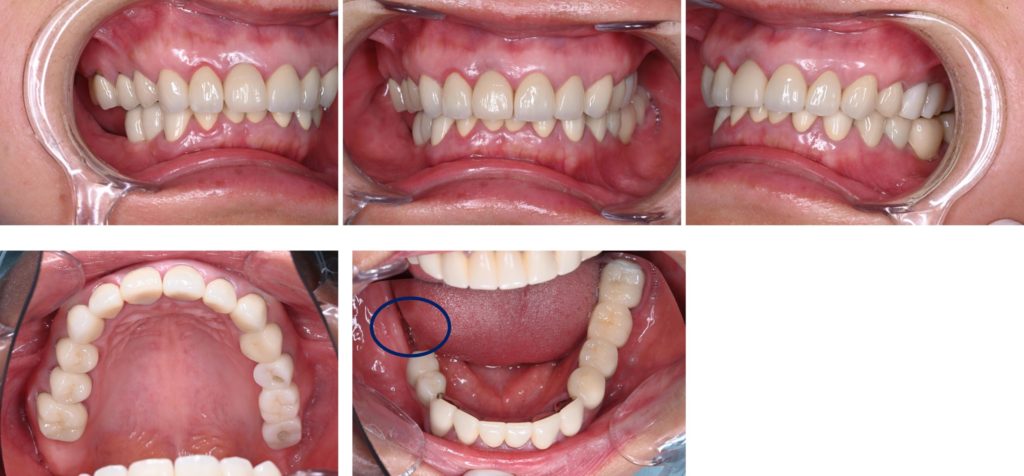

Before

| 診断名 | 臼歯部欠損および全顎的咬合崩壊 |

| 治療方法 | 当初は他院でインプラトができたいと言われた部分(右下)の骨造成処置後インプラト埋入手術を行なった。元々全てセラミックが入っていたが、全体的なバランス(咬合平面、咬合高径)、や歯の色に改善の余地があったため、患者との話し合いの上、可撤性のマウスピースでのトライ→接着性のトライ→セラミックへの置き換えを行なった(デジタルにて)。CADIAXにて術前、術中での顎運動の評価も行なった。 |